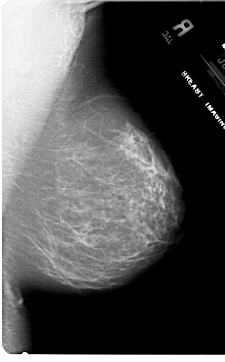

A_1787_1.RIGHT_CC

RIGHT_CC LINES 6871 PIXELS_PER_LINE 4096 BITS_PER_PIXEL 12 RESOLUTION 43.5 NON_OVERLAY